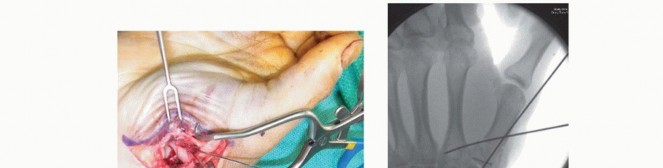

Open Reduction and Internal Fixation (ORIF) - Wagner Approach

For fractures with large volar-ulnar fragments (>20% of the articular surface), displaced Rolando fractures, or cases where closed reduction fails, ORIF is unequivocally mandated. The classic Wagner approach provides unparalleled exposure to the thumb CMC joint. A curvilinear incision is made along the glabrous border of the thenar eminence, curving dorsally at the level of the CMC joint.

Image

Meticulous superficial dissection is required to identify and protect the sensory branches of the superficial radial nerve dorsally and the palmar cutaneous branch of the median nerve volarly. The thenar musculature (abductor pollicis brevis and opponens pollicis) is sharply elevated from the metacarpal shaft and retracted volarly. The joint capsule is then incised longitudinally or in an L-shaped fashion to expose the articular surface. The hematoma is evacuated, and the fracture fragments are meticulously debrided of interposed soft tissue.

For a large fragment Bennett fracture, the shaft is reduced to the volar-ulnar fragment using a pointed reduction clamp. Provisional fixation is achieved with a K-wire. A 1.5mm or 2.0mm lag screw is then placed perpendicular to the fracture plane. The near cortex must be overdrilled (gliding hole) and the far cortex underdrilled (thread hole) to achieve true interfragmentary compression. The screw head should be countersunk to prevent hardware prominence beneath the thenar muscles.